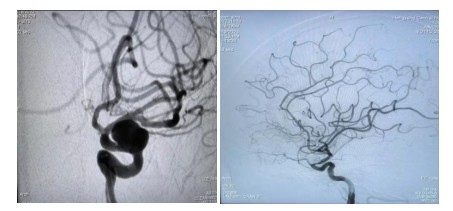

原來64歲的羅奶奶因?yàn)榘l(fā)現(xiàn)頸動(dòng)脈瘤10余天,來到衡陽市中心醫(yī)院全科醫(yī)學(xué)科住院,在完善腦血管造影檢查后,診斷其為左側(cè)頸內(nèi)動(dòng)脈眼動(dòng)脈段動(dòng)脈瘤,瘤體大,并有分葉子瘤,為高危破裂動(dòng)脈瘤。危急之下,轉(zhuǎn)入神經(jīng)內(nèi)科一病區(qū)準(zhǔn)備進(jìn)行介入手術(shù)治療。

經(jīng)過充分的術(shù)前準(zhǔn)備工作,神經(jīng)內(nèi)科中心主任丁菁帶領(lǐng)介入團(tuán)隊(duì)與導(dǎo)管室、麻醉科等多學(xué)科共同協(xié)作,順利為羅奶奶實(shí)施了血流導(dǎo)向密網(wǎng)支架輔助下顱內(nèi)動(dòng)脈瘤栓塞術(shù)。手術(shù)過程順利,術(shù)后羅奶奶在麻醉蘇醒后安返病房。在神經(jīng)內(nèi)科一病區(qū)醫(yī)護(hù)人員的精心護(hù)理下羅奶奶恢復(fù)良好,順利出院。